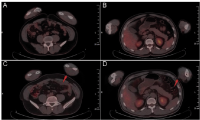

Fig. 2. PET-CT features of BPDCN. A and B is the negative control of C and D. C showed the disease’s relapse of the left forearm skin, D showed the lymph node involved in the ipsilateral elbow fossa.